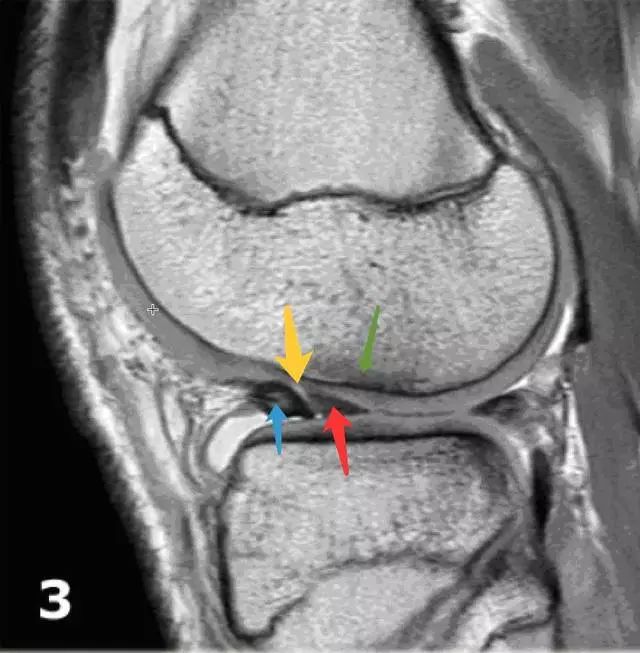

半月板翻转是一种特殊的半月板桶柄状撕裂。左图:可看到半月板前角(红色箭头)较大且边缘不规则,后角(蓝色箭头)较小。右图:半月板前角线性增强处(黄色箭头)易误诊为前角纵行撕裂,实际为前后角重叠的交界,其前方(蓝色箭头)为半月板前角,后方(红色箭头)是后角撕裂后翻转过来的部分。同时可看到局部的骨髓水肿和软骨压迫(绿色箭头)。